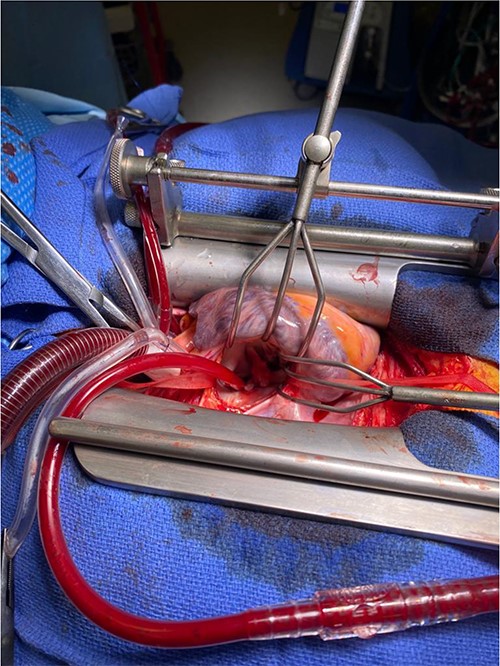

A CTPA was undertaken on Day 2, which excluded pulmonary embolism but confirmed bilateral peri-hilar consolidation and pleural effusions consistent with pneumonia. However, her pulmonary artery was dilated at 32 mm indicative of potential heart failure. On Day 5 of her ICU stay, a transthoracic echocardiogram was undertaken that revealed there to be severe mitral regurgitation including a mobile echogenic mass attached to the underside of the anterior mitral valve leaflet consistent with a vegetation (Figs 1 and 2).

Pre-operative TTE with Doppler depicting mitral valve with vegetation (labelled).

Intra-operatively, femoral–femoral bypass was established and a 3 cm windsock vegetation was found with a 1.5 × 1.5 cm hole at the aortic inlet on the annular junction. The vegetation travelled from the LV to LA as shown in Figs 3 and 4. The vegetation was excised and the valve debrided, which resulted in moderate regurgitation from severe. Hence, a further 26 mm Physio II ring was placed resulting in no mitral regurgitation. The excised vegetation is shown in Fig. 5 and the post-op TTE images are shown in Figs 6 and 7.